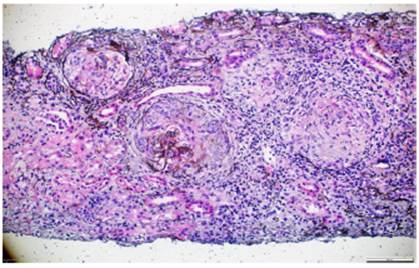

Se consideró que la paciente cursaba con GPA y se inició inmunosupresión con ciclofosfamida (en total 6 dosis de 10 mg/kg/dosis, cada 2 semanas las primeras 3 dosis y posteriormente cada tres semanas las otras 2 dosis) y rituximab (4 dosis semanales de 375 mg/m2/dosis). Sin embargo, a pesar del manejo instaurado, la paciente presentó un rápido deterioro de la función renal y requirió diálisis peritoneal.

La biopsia de piel de la lesión ulcerativa en muslo izquierdo tuvo un reporte de patología que mostró abundante infiltrado inflamatorio mixto de predominio polimorfonuclear supurativo, con áreas de ulceración extensa, tejido de granulación con proliferación de vasos y abundantes histiocitos. Adicionalmente, la biopsia renal reportó presencia de medialunas fibrocelulares en más del 50% de los glomérulos, proliferación de células mesangiales e inmunofluorescencia negativa para complejos inmunes (figs. 5 y 6).

Figura 5 Metenamina de plata. Glomérulos con presencia de semilunas fibrocelulares y necrosis fibrinoide en el penacho glomerular. 10x.

Figura 6 Metenamina de plata. Semiluna fibrosa con destrucción de la membrana basal glomerular y reemplazo de células epiteliales por fibroblastos en un proceso cicatricial. 40x.